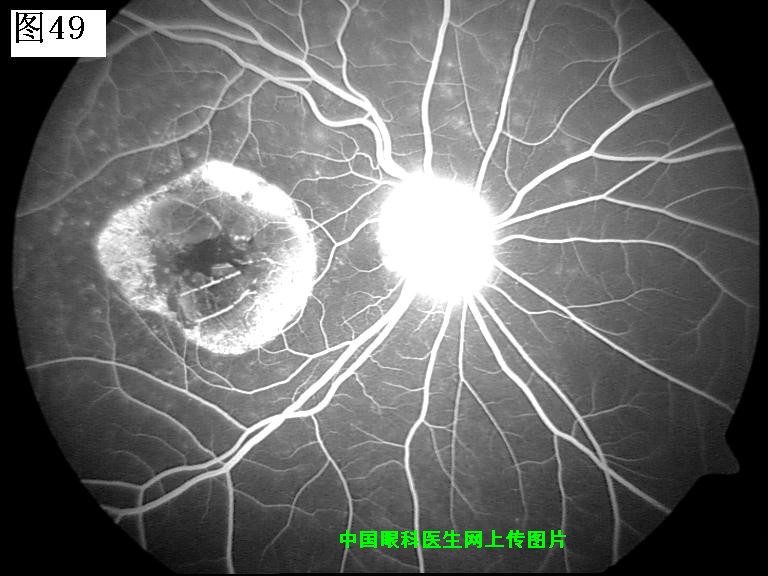

49 50 51 52